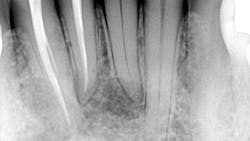

At her visit with me, the updated radiographs showed the presence of multilocular radiolucencies in the lower anterior area.Diagnosis and discussion